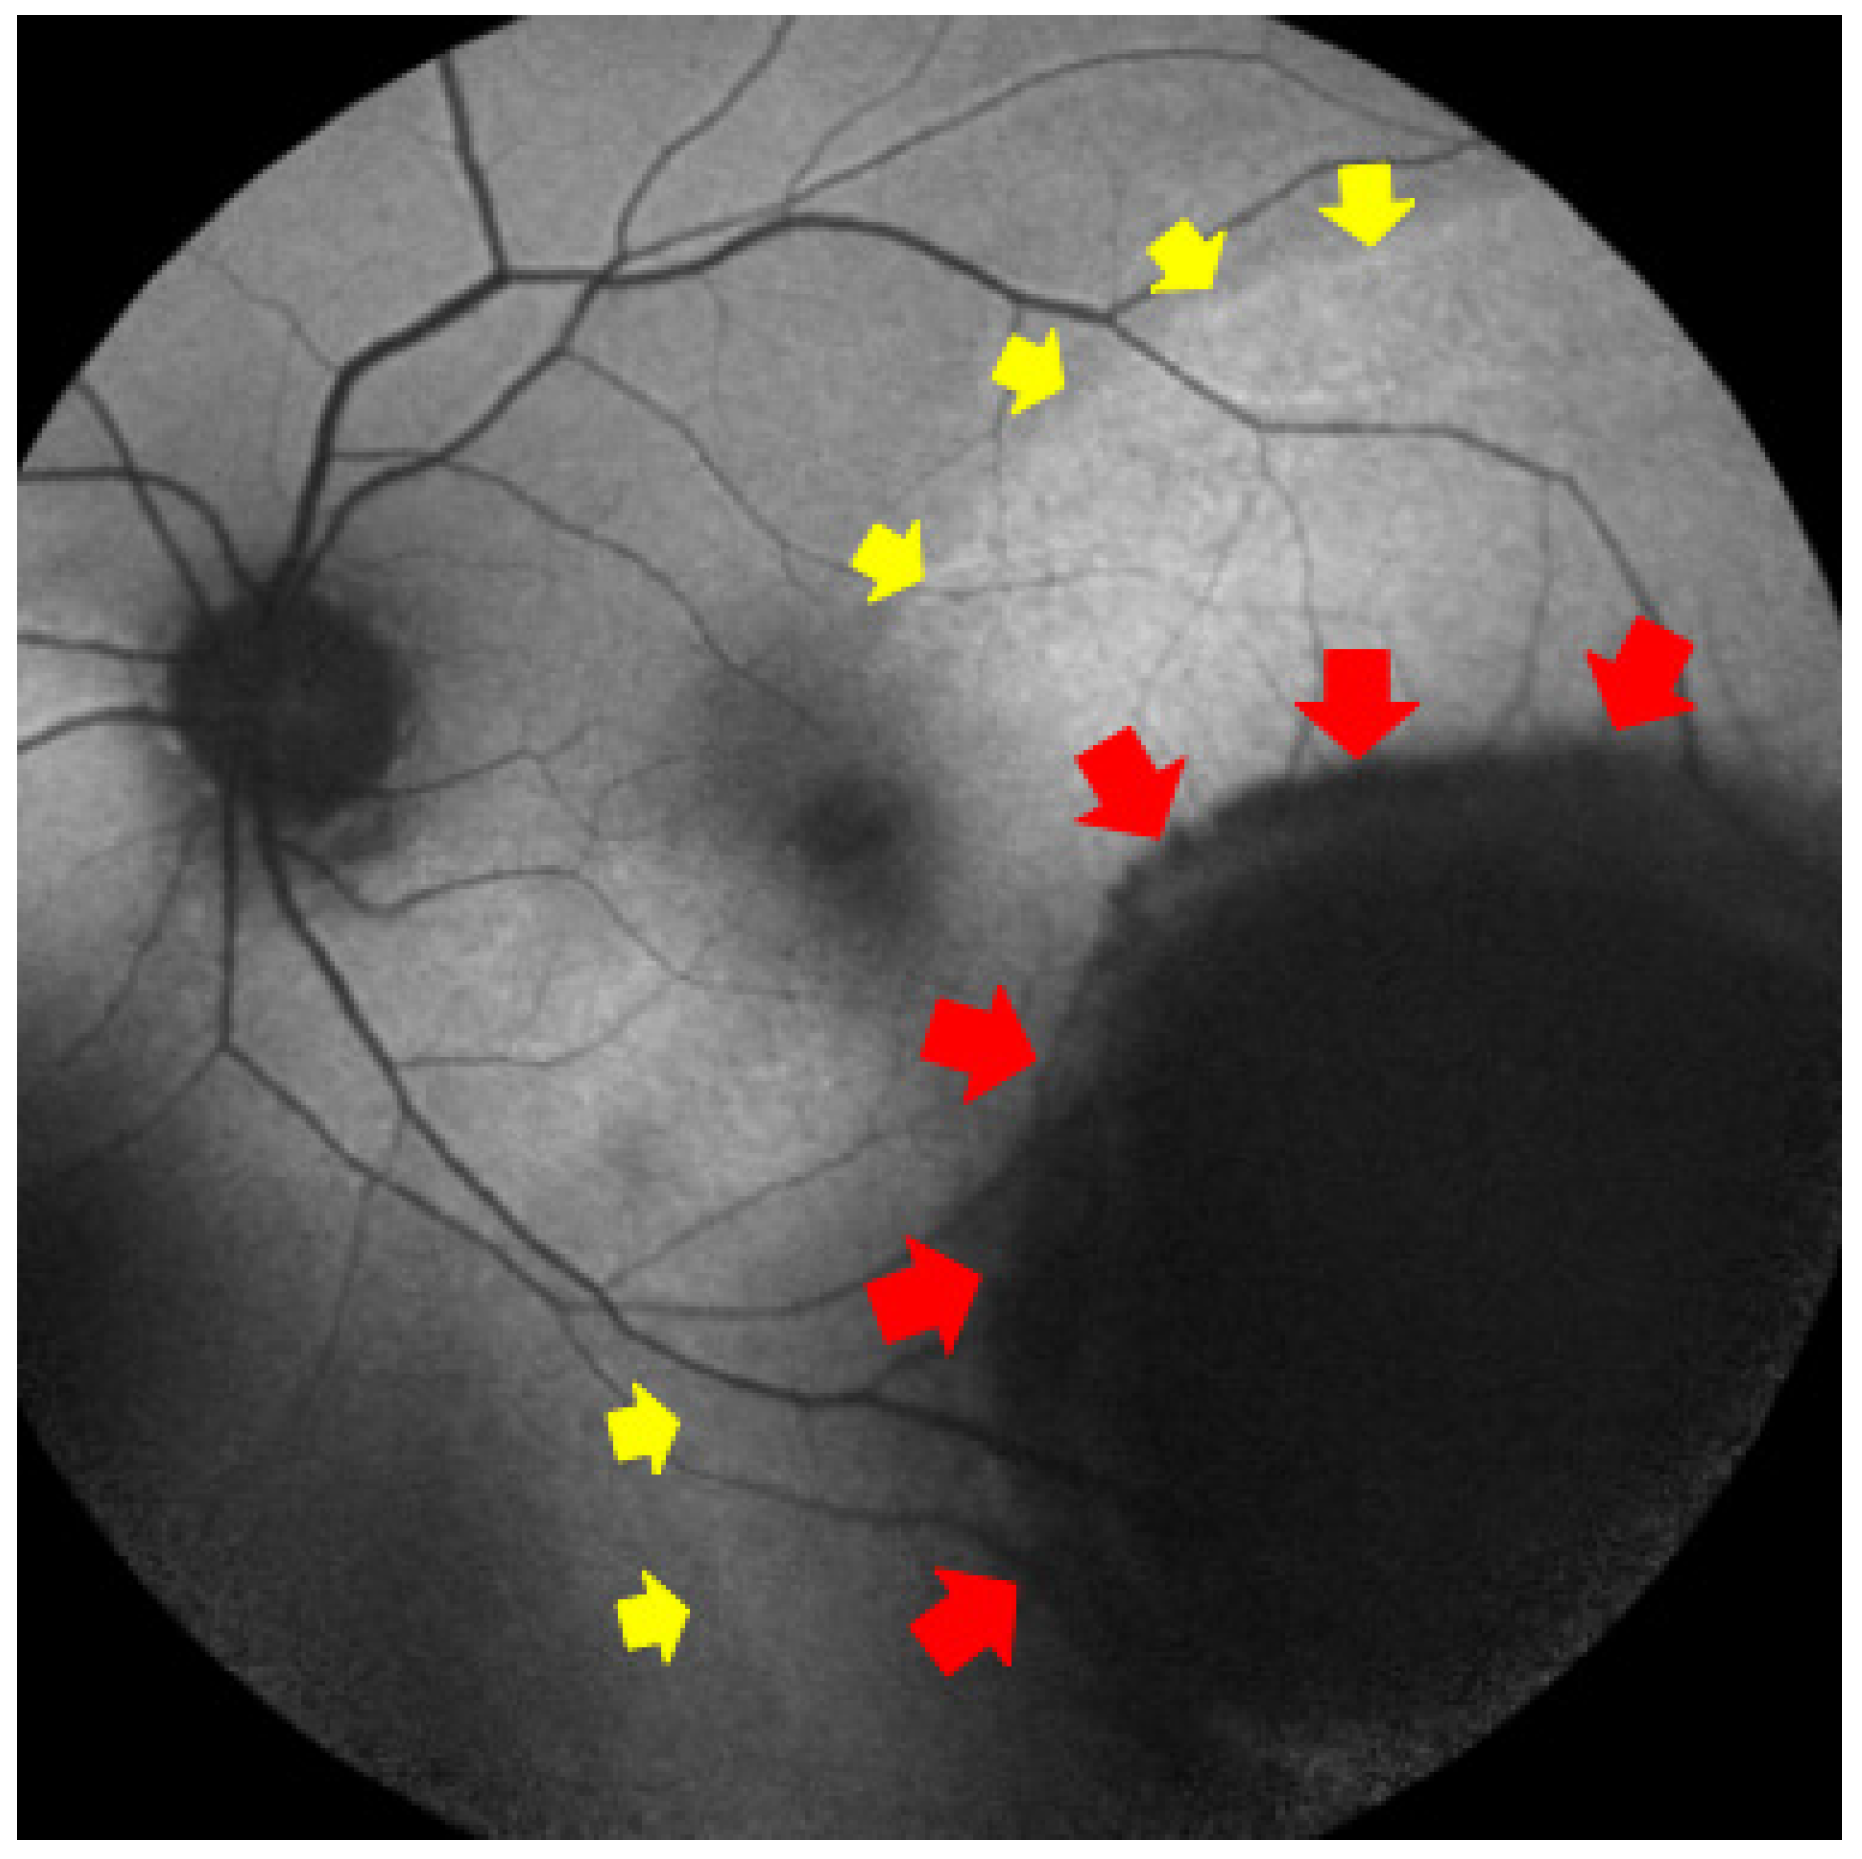

- Ghassemi, F.; Mirshahi, R.; Fadakar, K.; Sabour, S. Optical coherence tomography angiography in choroidal melanoma and nevus. Clin. Ophthalmol. 2018, 12, 207–214. [Google Scholar] [CrossRef]

| Intrinsic tumor vasculature grade (disorganized loops/networks) | SS-OCTA choroid slab; 6–12 mm; grading 0–4 | Higher grade (2–4) → melanoma vs. nevus; flags high-risk nevi | Differential diagnosis, risk stratification | Zhang et al., consecutive SS-OCTA cohort, n = 102: higher intralesional disorganization in melanomas; device-agnostic grading proposed; external validation pending [61]. Greig et al., small SS-OCTA series: qualitative differences between nevi and small melanomas [57]. |

| Patchy avascular areas at choriocapillaris over lesion | OCTA choriocapillaris slab | Presence/greater extent → melanoma over nevus | Differential diagnosis | Zhang et al., n = 102: lesion-overlying CC avascular patches more frequent in melanoma [61]; corroborated by smaller SS-OCTA case series [57,60]. |